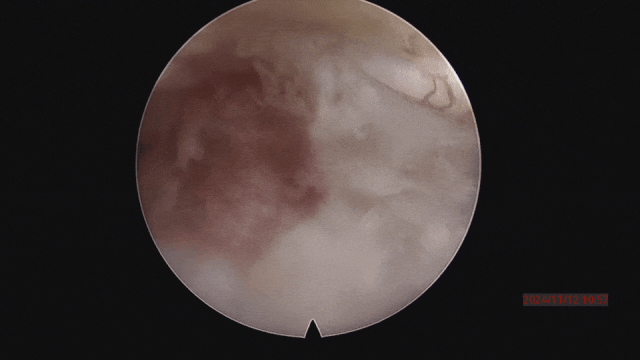

▲取之前,骨塊突入椎管、壓迫神經。